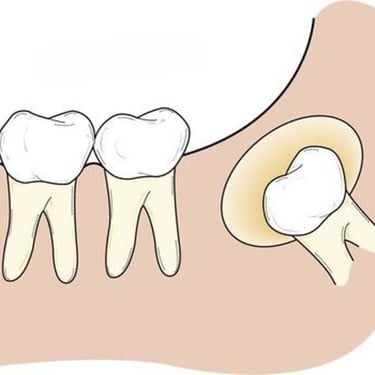

Dientes impactados

Los dientes impactados son dientes que no pueden erupcionar correctamente debido a la falta de espacio o a una obstrucción.

Los pacientes pueden notar que un diente no ha salido, aunque debería haberlo hecho. Esta condición es común con las muelas del juicio y los caninos superiores.

El tratamiento puede incluir la extracción del diente impactado o la creación de espacio para permitir su erupción.